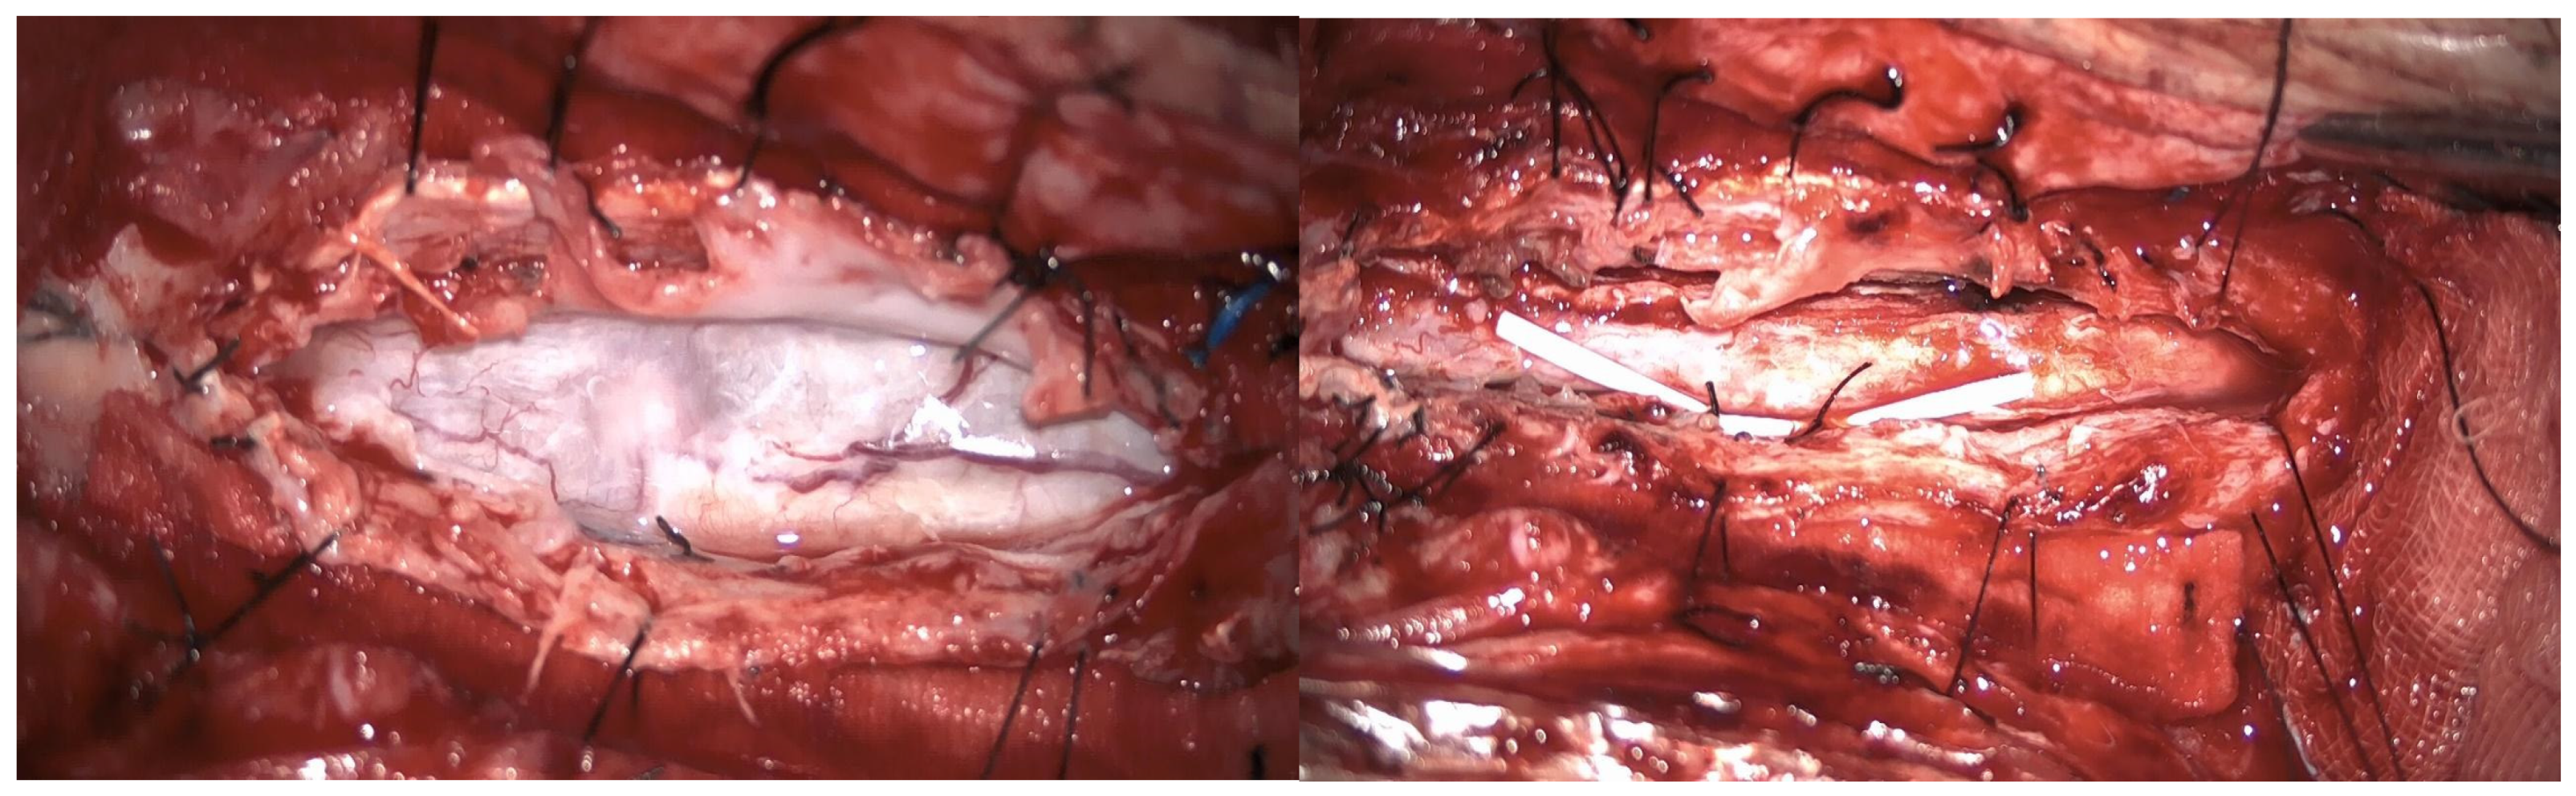

3.4.1. Case 1

| Surgical treatment | lysis of adherences and syrinx cavity opening | resection of the cystic formation and adhesiolysis | resection of the cystic formation and adhesiolysis | resection of the cystic formation and adhesiolysis | resection of the cystic formation and adhesiolysis |

| Complications | CSF fistula | infection | None | CSF fistula | None |

| KPS pre-op (%) | 70 | 50 | 70 | 80 | 90 |

| KPS post-op (%) | 80 | 50 | 60 | 90 | 80 |

| ASIA score pre-op | C | B | B | C | D |

| ASIA score post-op | D | B | C | C | D |